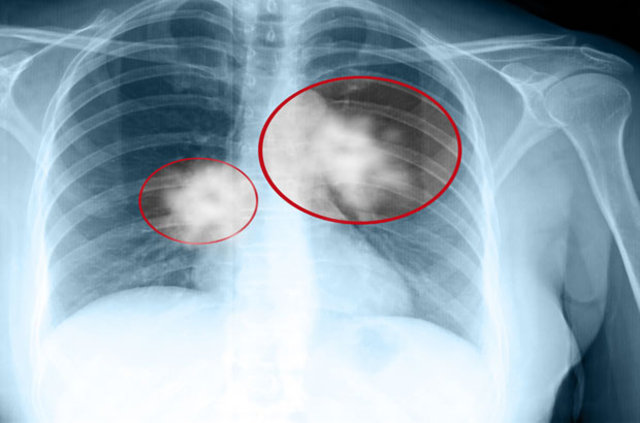

Göğüs Hastalıkları Uzmanı Prof. Dr. Necla Songür, “17 Kasım Dünya Akciğer Kanseri Günü” nedeniyle, akciğer kanseri ile doğrudan ilişkili olabilecek risk faktörleri ve akciğer kanserinden korunmanın yolları hakkında bilgi verdi.

GÜNDE BİRKAÇ SİGARA BİLE KANSERE YAKALANMA RİSKİNİ ARTIRIR

Sigara içmek akciğer kanseri için bir numaralı risk faktörüdür. Pipo ve puro benzeri tütün ürünlerinin kullanılması ve ikinci el sigara dumanına maruz kalmak akciğer kanseri riskini artırmaktadır.

Sigara içenler, sigara içmeyenlere göre 15 ila 30 kat daha fazla akciğer kanserine yakalanmaktadır. Günde birkaç sigara içilmesi bile akciğer kanseri riskini artırır. Her yaşta sigarayı bırakmak akciğer kanserinden korunmak için en önemli adımdır.